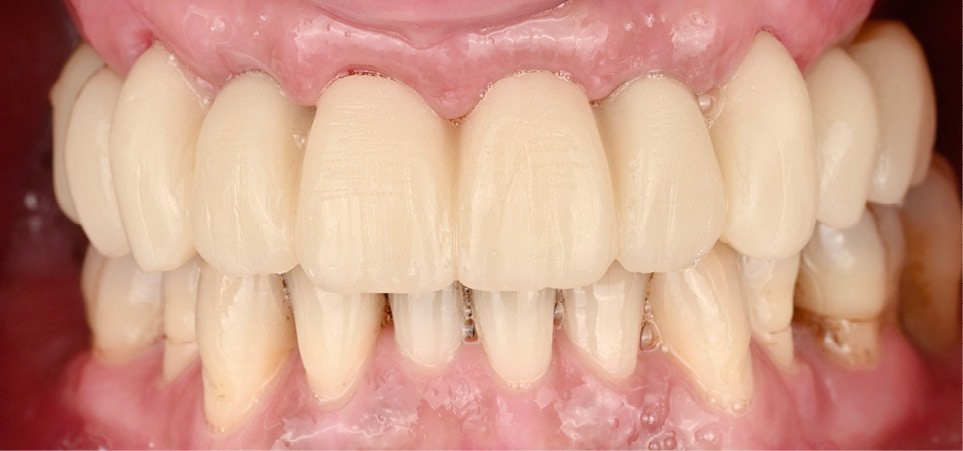

Une empreinte numérique du positionnement des implants a été réalisée pour la conception d’une seconde prothèse transitoire guidant la cicatrisation. Cette restauration a permis de sculpter progressivement les tissus mous pour obtenir une émergence harmonieuse (fig. 7). Ces ajustements successifs ont favorisé la stabilité des papilles et la continuité du contour gingival (fig. 8) [3].

Elle est réalisée en zircone monolithique usinée puis stratifiée manuellement (fig. 9). Dans cette approche hybride numérique-analogique, la CFAO assure la précision de la structure, tandis que la stratification manuelle apporte la personnalisation esthétique et la vitalité du rendu [4]. Le résultat illustre la convergence entre précision technologique et sensibilité clinique (fig. 10).